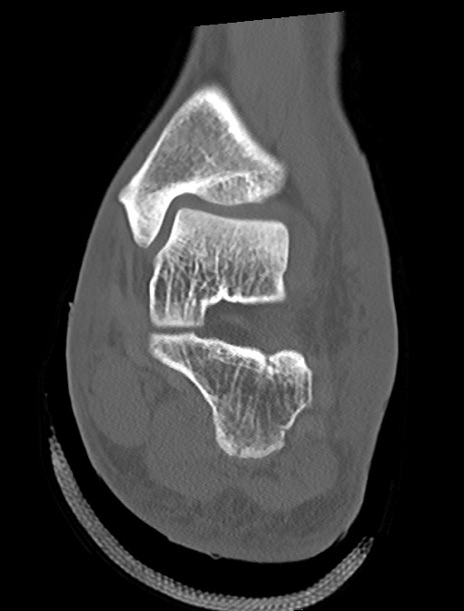

左足関節CT

矢状断像